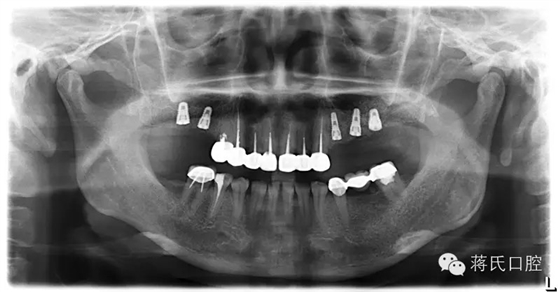

種植前X線(xiàn),左側(cè)外提升右側(cè)內(nèi)提升

13.種植完成后X

19.修復(fù)完成后X